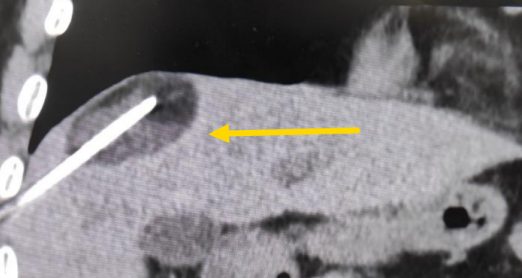

這個(gè)患者病變位置刁鉆,穿刺難度大,冷凍消融的難點(diǎn)在于既要不損傷膈肌和肺組織,同時(shí)又要盡最大可能完全消融腫瘤。術(shù)前陳寶瑩主任、李鐵柱教授、兀云飛醫(yī)生詳細(xì)設(shè)計(jì)進(jìn)針路徑、布針計(jì)劃,術(shù)中微創(chuàng)團(tuán)隊(duì)協(xié)調(diào)配合,李鐵柱教授仔細(xì)操作,精準(zhǔn)到位,順利完成兩個(gè)病變的布針,遂啟動(dòng)治療,先快速降溫到-150多度,再升溫至15?,經(jīng)過(guò)兩個(gè)循環(huán)反復(fù),即刻觀察到病變完全被冰球覆蓋,同時(shí)周?chē)K器無(wú)損傷,術(shù)中患者幾乎沒(méi)有疼痛,還和醫(yī)生聊起了天。

術(shù)中冰球形成